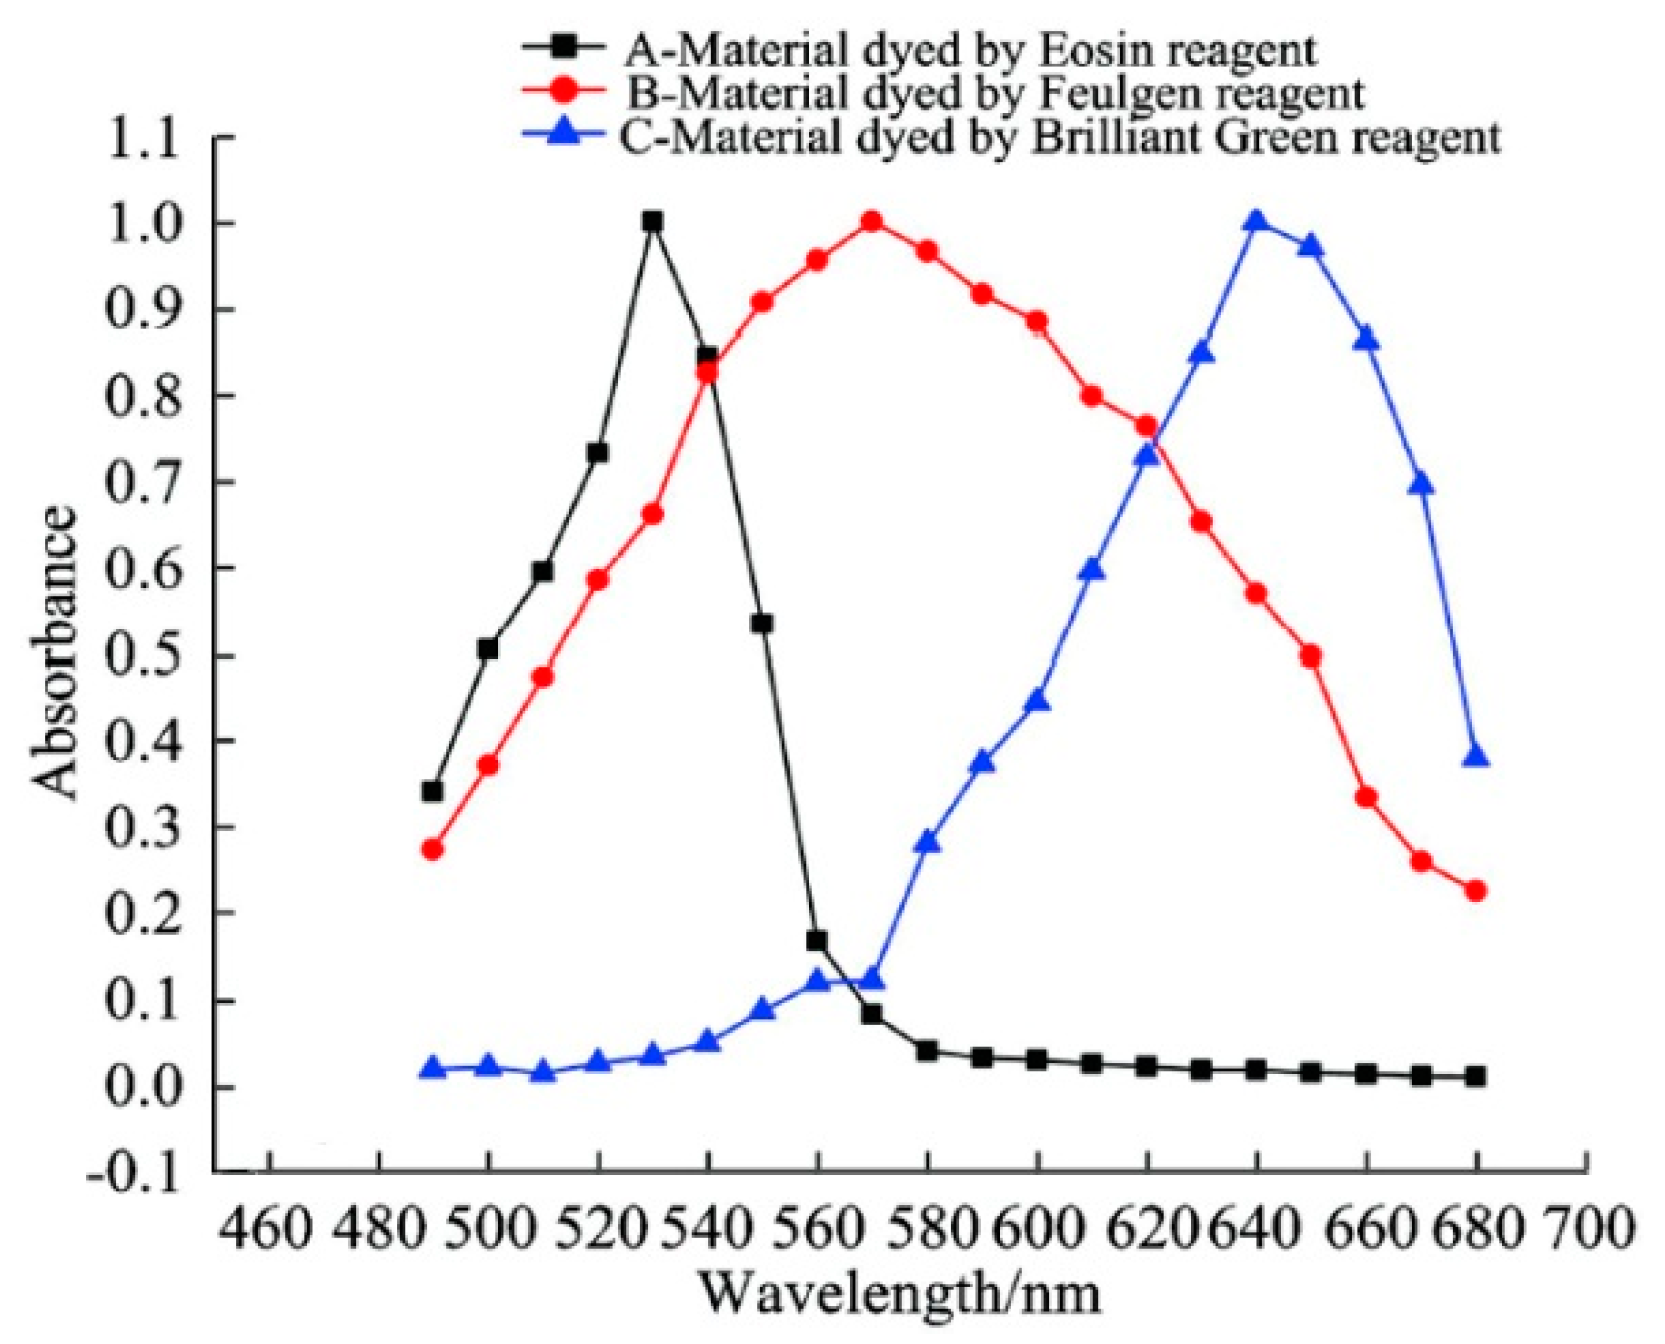

2.2. Multi-Spectral Absorbance Unmixing Model

3.1. Pseudo-Color Image Synthesizing and Absorbance Unmixing